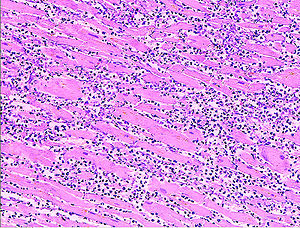

Histopathology

Histopathological examination of the heart may reveal infarction at autopsy. Under the microscope, myocardial infarction presents as a circumscribed area of ischemic, coagulative necrosis (cell death). On gross examination, the infarct is not identifiable within the first 12 hours.

Although earlier changes can be discerned using electron microscopy, one of the earliest changes under a normal microscope are so-called wavy fibers. Subsequently, the myocyte cytoplasm becomes more eosinophilic (pink) and the cells lose their transversal striations, with typical changes and eventually loss of the cell nucleus. The interstitium at the margin of the infarcted area is initially infiltrated with neutrophils, then with lymphocytes and macrophages, who phagocytose ("eat") the myocyte debris. The necrotic area is surrounded and progressively invaded by granulation tissue, which will replace the infarct with a fibrous ( collagenous) scar (which are typical steps in wound healing). The interstitial space (the space between cells outside of blood vessels) may be infiltrated with red blood cells.

These features can be recognized in cases where the perfusion was not restored; reperfused infarcts can have other hallmarks, such as contraction band necrosis.